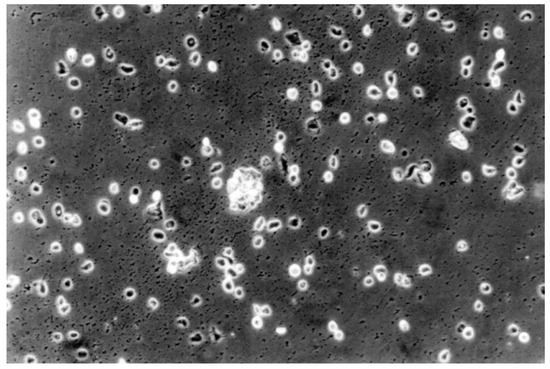

2.2.2. Qualitative Evaluation

| 3 | moderate | Not more than 70% of the cell layers contain rounded cells or are lysed; cell layers not completely destroyed, but more than 50% growth inhibition observable |

| 4 | severe | Nearly complete or complete destruction of the cell layers |